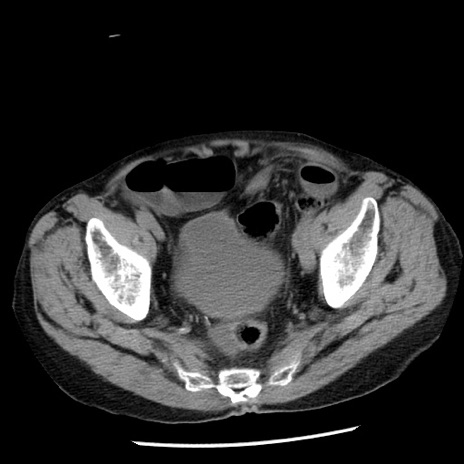

冠状断像

症例26(横断像)

【症例】80歳代男性

【主訴】嘔吐

【現病歴】昨晩2回嘔吐あり、今朝になっても嘔吐あり。来院。

【既往歴】胃潰瘍

【身体所見】意識清明、BT 37.6℃、BP 166/95mmHg、HR 100bpm、SpO2 97%、腹部:平坦・軟、腸蠕動音聴取良好、圧痛なし。

【データ】WBC 21900、CRP 1.46